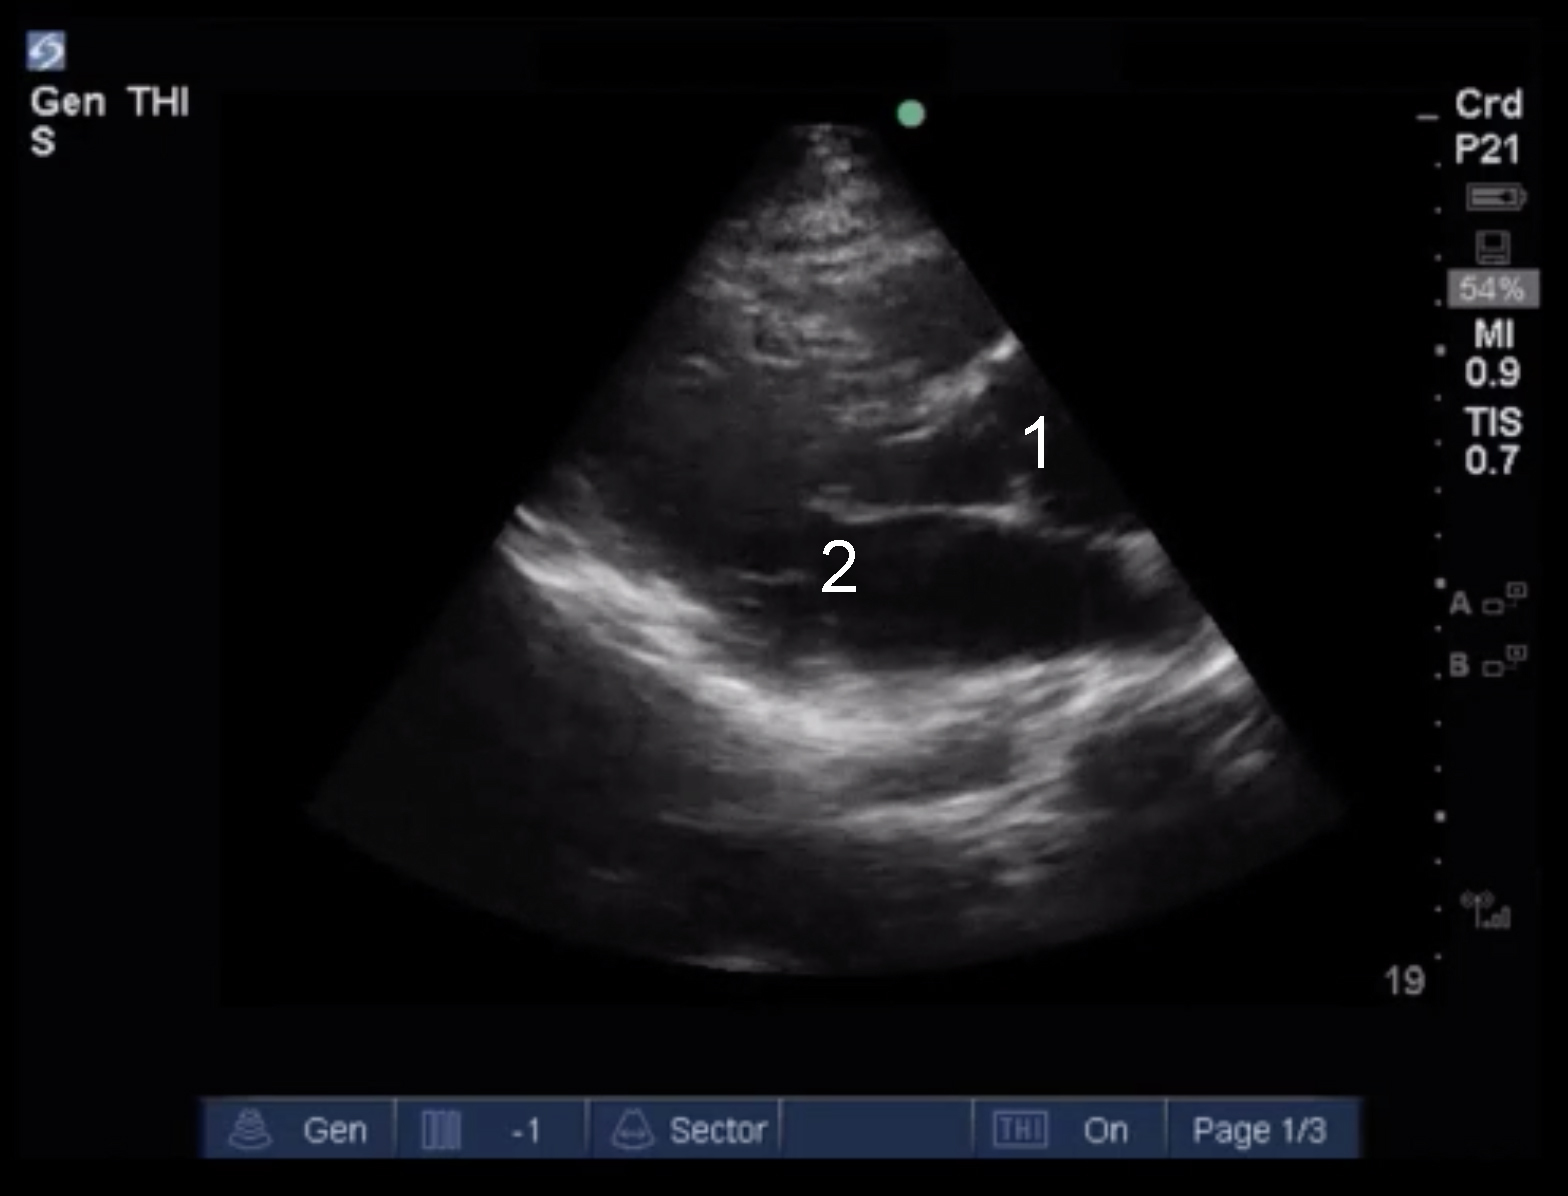

Cardiac 2 Valves Eyeball Assessment Example 4 Image

Aortic Valve

Mitral Valve